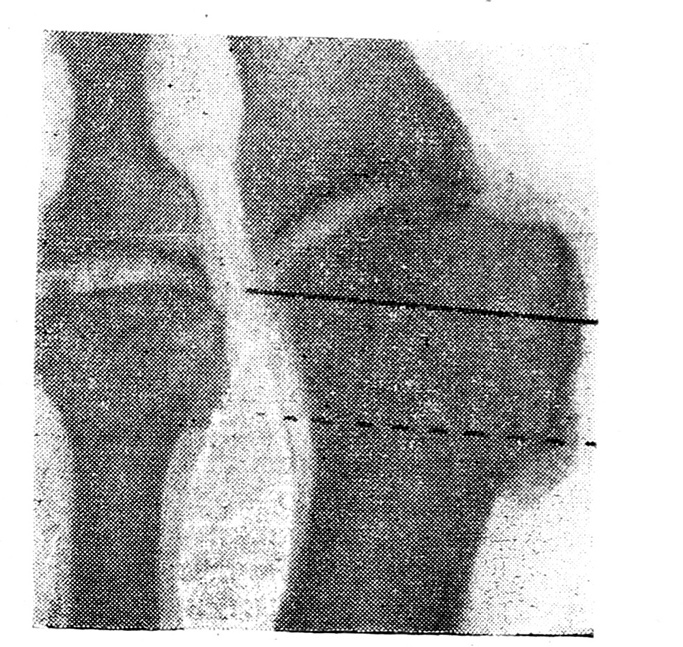

Мы видоизменили этот способ. Головку I плюсневой кости удаляем не у ее основания вместе с экзостозом, как рекомендовал Р. Р. Вреден (рис. 1), а только часть ее, покрытую хрящом, а экзостоз скусываем дополнительно. Удаление головки производится не щипцами Листона, а пилкой Джигли. По нашим наблюдениям, удаления только хрящевой части головки вполне достаточно для разгрузки мышц большого пальца и его коррекции в нормальном положении, кроме того — сохраняется точка опоры на вновь образованный I плюсне-фаланговый сустав. Спиливание головки ускоряет операцию, оно менее травматично, не оставляет даже мельчайших костных шипов, остающихся при скусывании и травмирующих хрящевую поверхность 1 фаланги, вызывая тем значительные боли.

Рис. 1